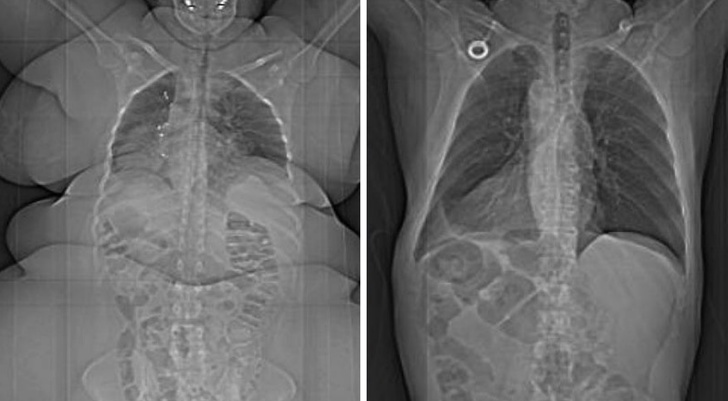

8. A gauche, un corps en surpoids. À droite, un corps normal !

Illustration de l'article : Ces 15 photos qui en disent beaucoup sur le corps humain

© Unknown / Reddit